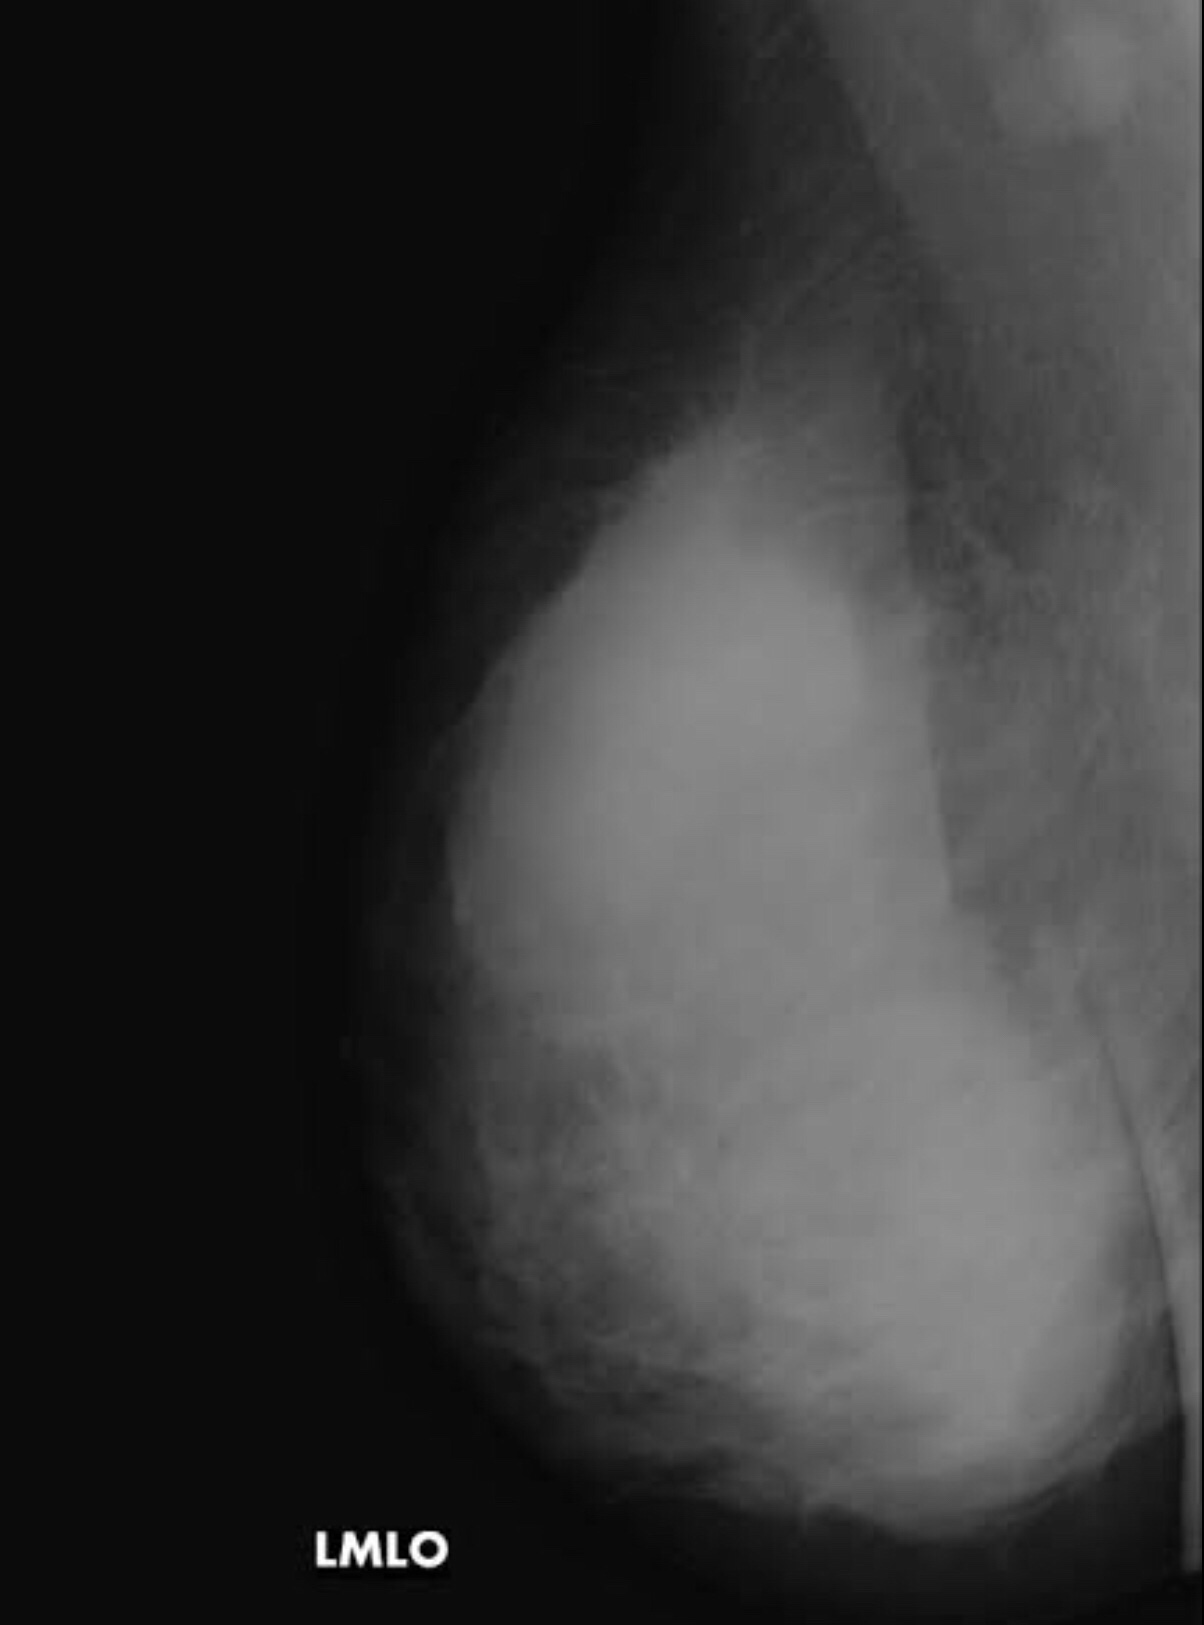

Correct positioning of the breasts would be very important in obtaining good pictures. In the MLO views the Pectoral muscle shadow must be seen and the breast must be adequately compressed to get the best pictures. Inadequate compression would cause superimposition of the tissues